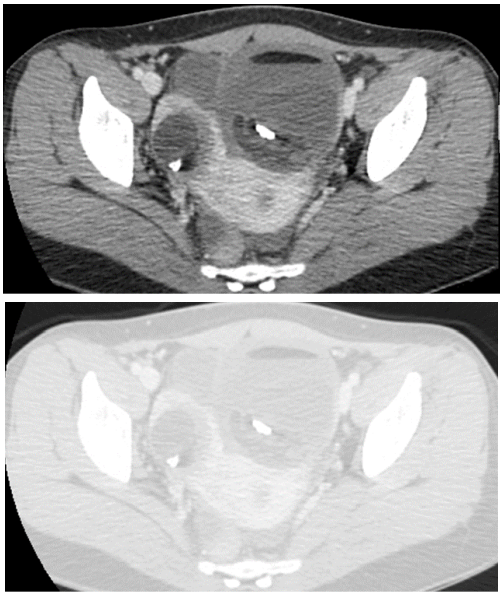

75 一位 64 歲女性因腹膜炎接受電腦斷層檢查,發現子宮內有置入避孕器線圈(IUD)如下圖箭號所 指,下列敘述何者錯誤?

(A)子宮膿瘍 (B)子宮內膜異位 (C)子宮壞死穿孔 (D)腹膜膿瘍